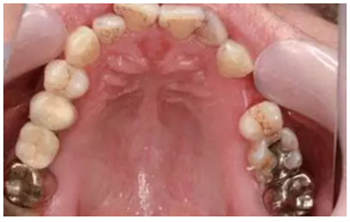

術(shù)前拍攝錐形束CT并做種植方案規(guī)劃。從圈紅處可以看出頰側(cè)骨組織不夠致密,建議備完孔后再做小翻瓣以觀察窩洞頸部的情況,圖2中的粉紅色及藍(lán)色HU值曲線顯示種植體內(nèi)部及其周圍的骨密度不高,為四類骨質(zhì),因此術(shù)中應(yīng)通過控制備孔的直徑或深度,以使種植體獲得較佳的初期穩(wěn)定性。

圖2 種植方案的規(guī)劃:a.頰舌側(cè)方向的截面圖,頰側(cè)圈紅處骨質(zhì)較疏松;b.近遠(yuǎn)中方向截面圖;c.種植體周圍的骨密度